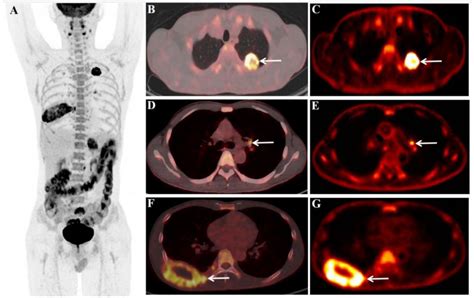

PET-CT scans are a powerful diagnostic tool that combines the strengths of both PET and CT scans. PET scans use a radioactive tracer to highlight areas of high metabolic activity, which is often indicative of cancer cells. CT scans, on the other hand, provide detailed anatomical images of the body. When combined, PET-CT scans offer a comprehensive view of both the structure and function of the body's tissues, making them invaluable in the diagnosis and staging of Pet Ct Lung Cancer.

PET-CT scans involve the injection of a radioactive tracer, typically a form of glucose, into the patient's bloodstream. Cancer cells, which have a higher metabolic rate, absorb more of the tracer than normal cells. The PET scanner then detects the radiation emitted by the tracer, creating images that highlight areas of high metabolic activity. Simultaneously, the CT scanner takes detailed images of the body's structures, which are then fused with the PET images to provide a precise location of the cancerous cells.

• Accurate Staging: The detailed images provided by PET-CT scans help in accurately staging the cancer, which is crucial for determining the appropriate treatment plan. Staging involves assessing the size and extent of the tumor, as well as whether it has spread to other parts of the body.

• Treatment Monitoring: PET-CT scans can be used to monitor the effectiveness of treatment by comparing images taken before and after therapy. This helps in adjusting treatment plans as needed.

Interpreting the results of a PET-CT scan involves a detailed analysis by a radiologist. The images are reviewed to identify areas of high metabolic activity, which may indicate the presence of cancer. The results are then shared with the patient's healthcare team, who will discuss the findings and develop a treatment plan. It is important to note that while PET-CT scans are highly accurate, they are not foolproof. False positives and false negatives can occur, and additional tests may be needed to confirm the diagnosis.